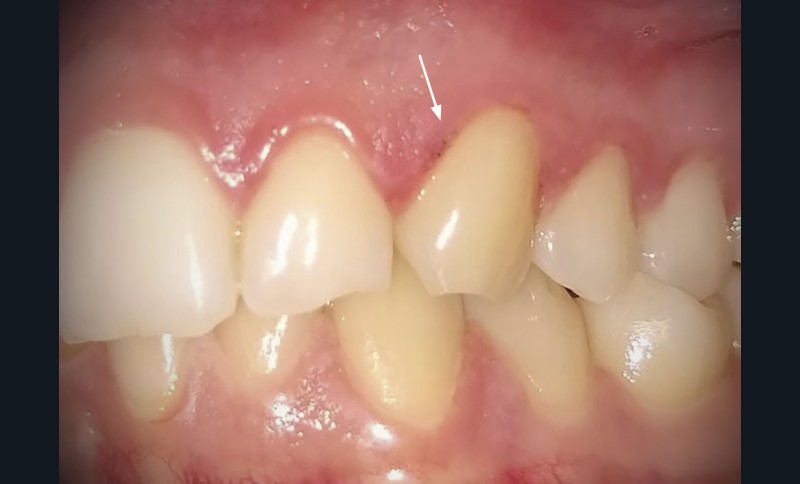

Présence de zones d’érosions post-vésiculeuses regroupées en « bouquet » en palatin des 12, 11 et 22 (fig. 1a) et au niveau de la gencive marginale de la 23 (fig. 1b). Les muqueuses affectées étaient enflammées et sensibles au toucher. Pas d’adénopathie cervico-faciale palpable et pas d’atteinte extra-orale.